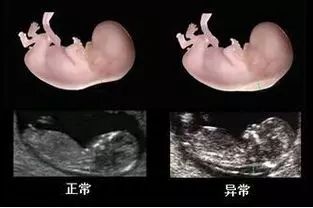

划重点:NT测值大于3毫米为异常,这个数值越高,胎儿出现异常的风险越高。

正常和异常的区别